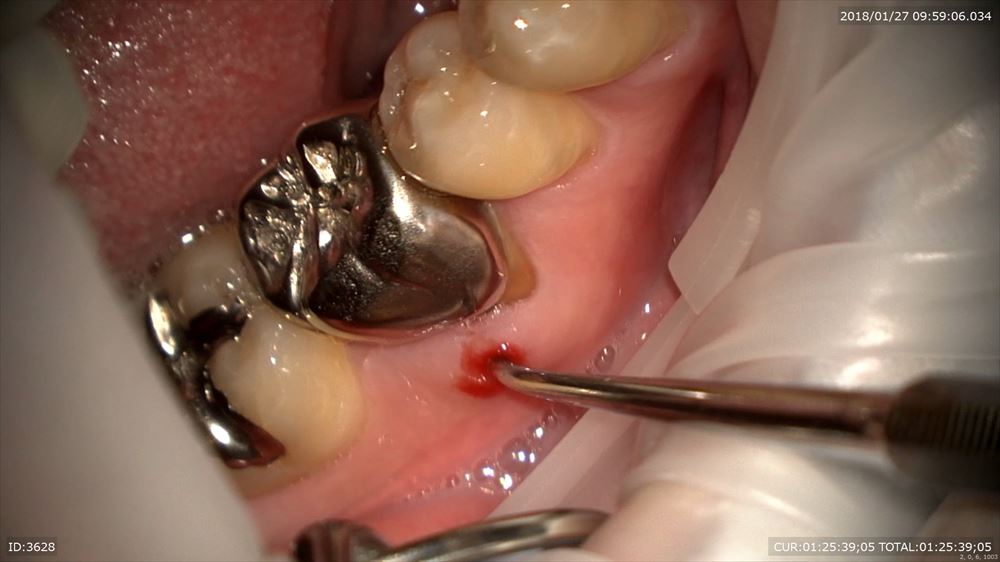

根管治療で潰瘍は2回で治り

この様に仮歯で2ヶ月観察。問題なし。歯周病学会認定衛生士の歯周治療後私に昨日帰ってきました。